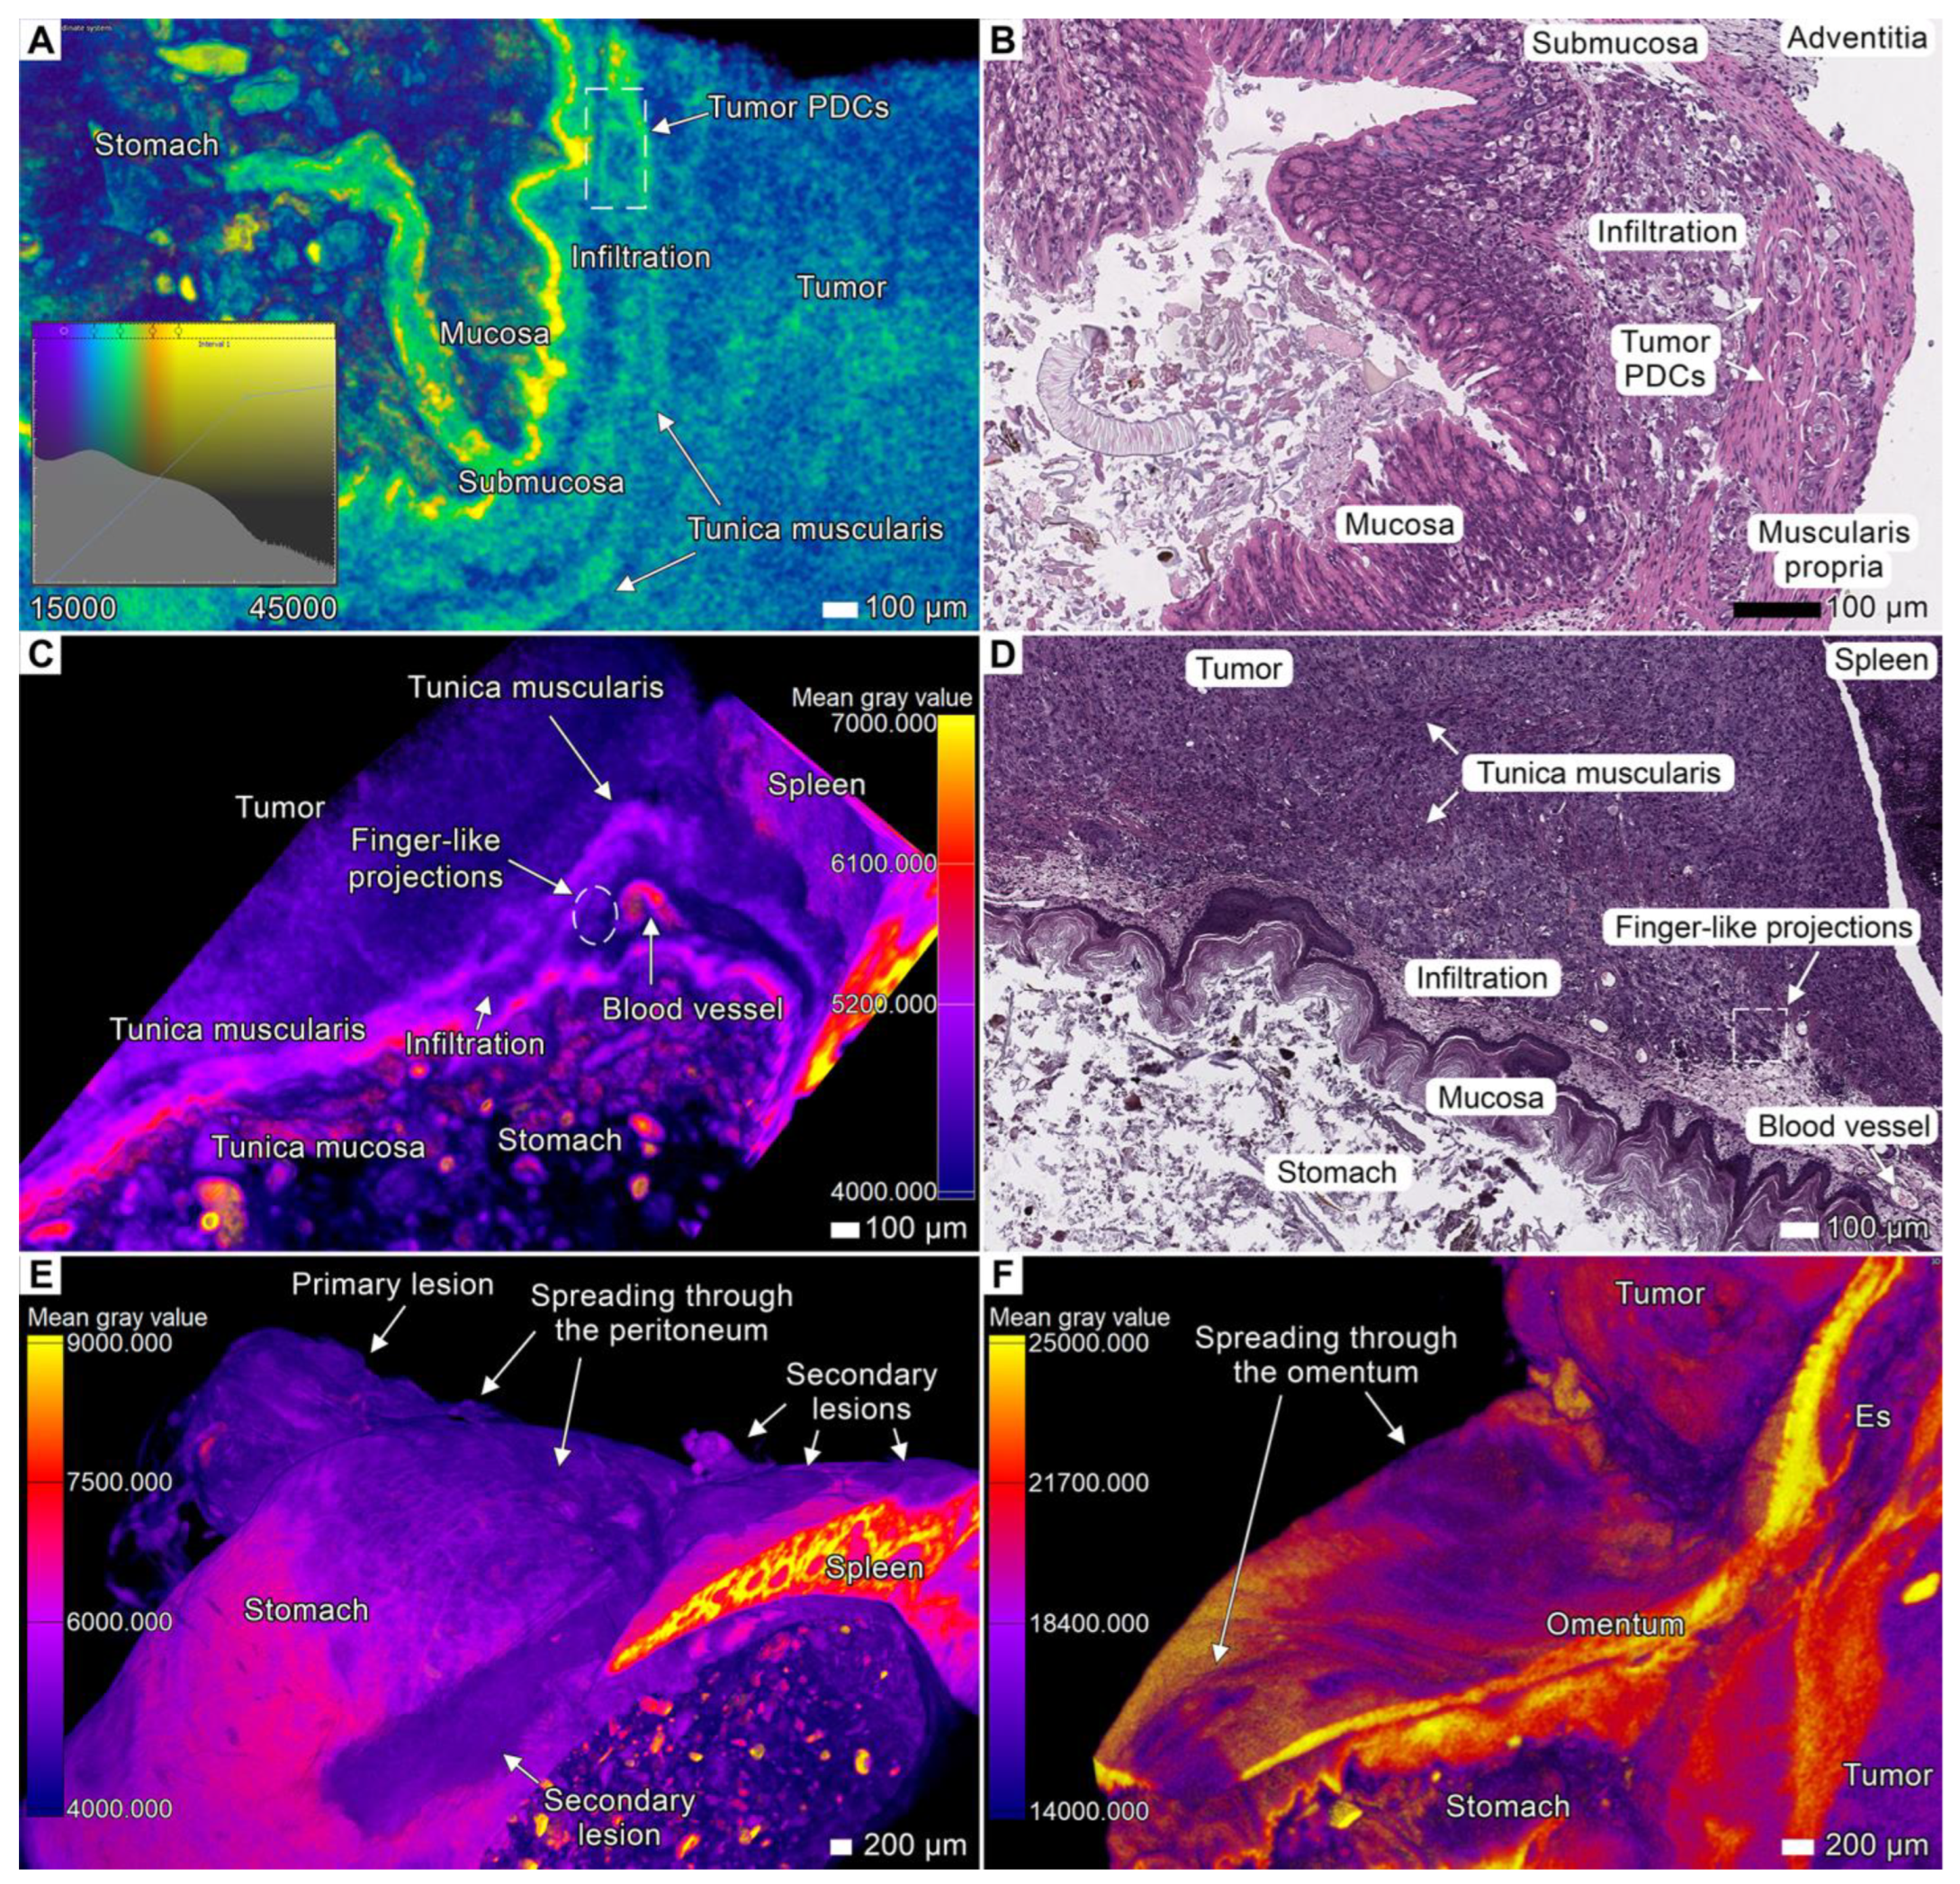

3.2. Tumor Invasion into the Esophagus and Stomach

3.3. Tumor Invasion into the Spleen

3.6. Peritoneal Dissemination